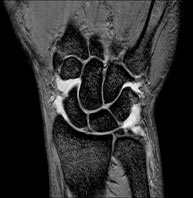

Exploració per a l'estudi de lesions en els tendons, els músculs i els nervis perifèrics. La durada aproximada és de 18 minuts. No utilitza radiació ionitzant. - RM Canell /carp

Exploració per a l'estudi de lesions en els tendons, els músculs i les articulacions. Molt útil per a la valoració de petites fractures inadvertides, lesions de lligaments i processos inflamatoris i degeneratius (artritis i artrosi). La durada aproximada és de 20 minuts. No utilitza radiació ionitzant. - RM de Mà / dits